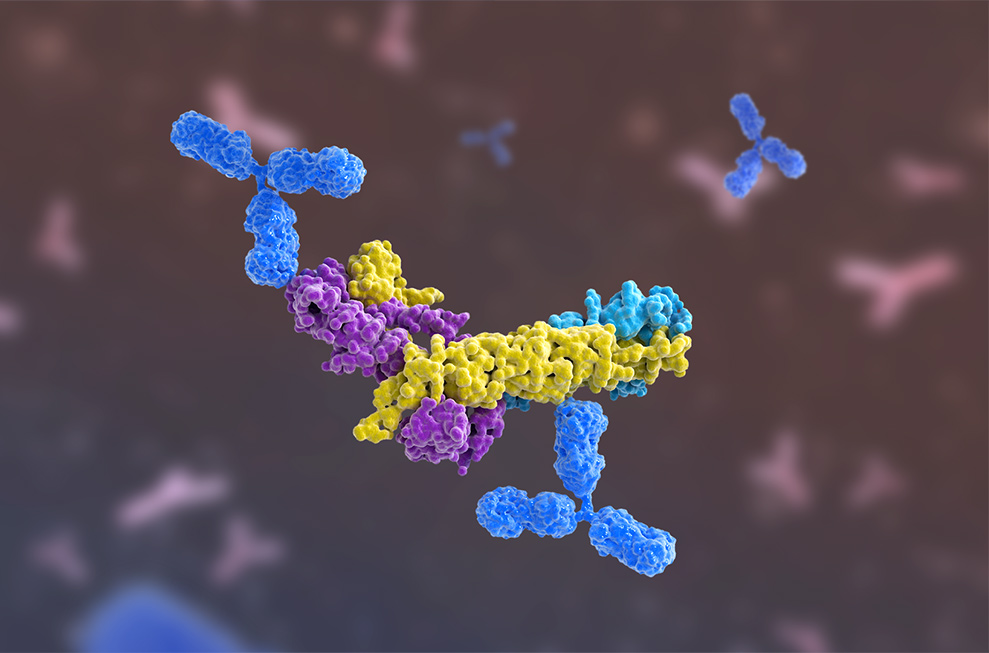

This sculpture is now standing in the IVD exhibition hall at Mindray's headquarters. When you look at the sculpture closely, you can see that its central part is like an irregular "paper cluster" formed by interlaced three-color wooden pieces. It is held firmly by the Y-shaped "tentacles" at the upper and lower ends.

"Truth Capturer" ŌĆö Antigen-Antibody Detection Model Sculpture

This structure is inspired by the detection model of the cardiac marker ŌĆö troponin, where the detection and capture antibodies work together to capture antigen complexes. The combination of the beveled, flipped wooden pieces reproduces the dynamic, folded structure of the proteins.

Scientists observed that after the onset of myocardial infarction, troponin is released from the heart into the peripheral circulation, and its complexes would appear in different forms over time. For over two decades, HyTest's moving increasingly close to the truth has pushed it into rethinking how to identify highly specific antibodies that can adapt to changes and deliver accurate test results.

Since troponin exists in a variety of forms, it is necessary to build a combat system to recognize complexes.

Based on the research on complexes, the scientists started to experiment on the recognition sites to identify the optimal capture/detection antibody pair. They intended to come up with a "proactive and adaptable" tactic to eliminate interferences and precisely capture targets in the molecular stabilization region.